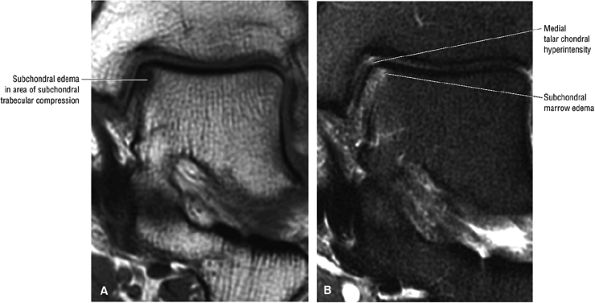

FIGURE 5.95 ● Stage I OLT with subchondral bone marrow edema, which is hypointense on the coronal T1-weighted FSE image (A) and hyperintense on the coronal FS PD FSE image (B). The overlying talar articular cartilage is hyperintense on the FS PD FSE image (B).